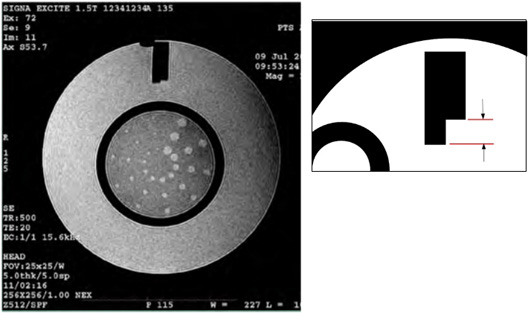

Slice Position Accuracy

Slices 1 and 11 were prescribed to be aligned with the vertices of the crossed 45 degree wedges at the inferior and superior ends of the phantom respectively. On the images of slices 1 and 11 the crossed wedges appear as a pair of adjacent, dark vertical bars at the top (anterior side) of the phantom. See illustration below. A perfectly positioned slice’s image shows a dark bar pair with left and right sides of equal vertical length. If the slice is displaced superiorly with respect to the vertex, the bar on the observer’s right (anatomical left) is longer. If the slice is displaced inferiorly with respect to the vertex, the bar on the left (anatomical right) will be longer.

Referring to Figure 18, use the on-screen length measurement tool to measure the difference in vertical lengths between the left & right bars of the cross wedge in mm.

Record the difference (as a negative value if the left bar is longer) as ACR T1 Slice 1 Bar Length Difference (mm). Use the ACR Accreditation Scan Measurements form to record the values.